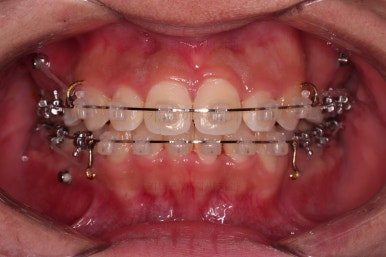

초진 시 입안의 모습입니다.

앞니가 많이 삐뚤고, 송곳니가 부각되어 덧니처럼 보이네요.

장치를 처음 부착한 모습입니다.

이번 환자분이 선택하신 장치는 데이몬 클리어라고 하는 자가결찰 세라믹 장치인데요.

흔히들 아시는 클리피씨 장치 등등에 비해 현존하는 브라켓 중에 가장 심미적인 장치입니다.